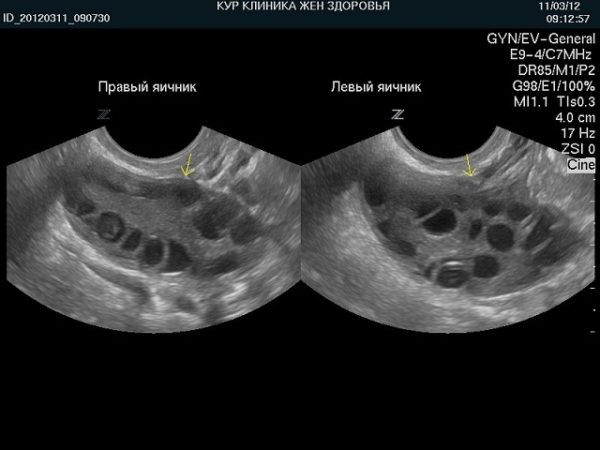

- УЗИ, КТ, МРТ;